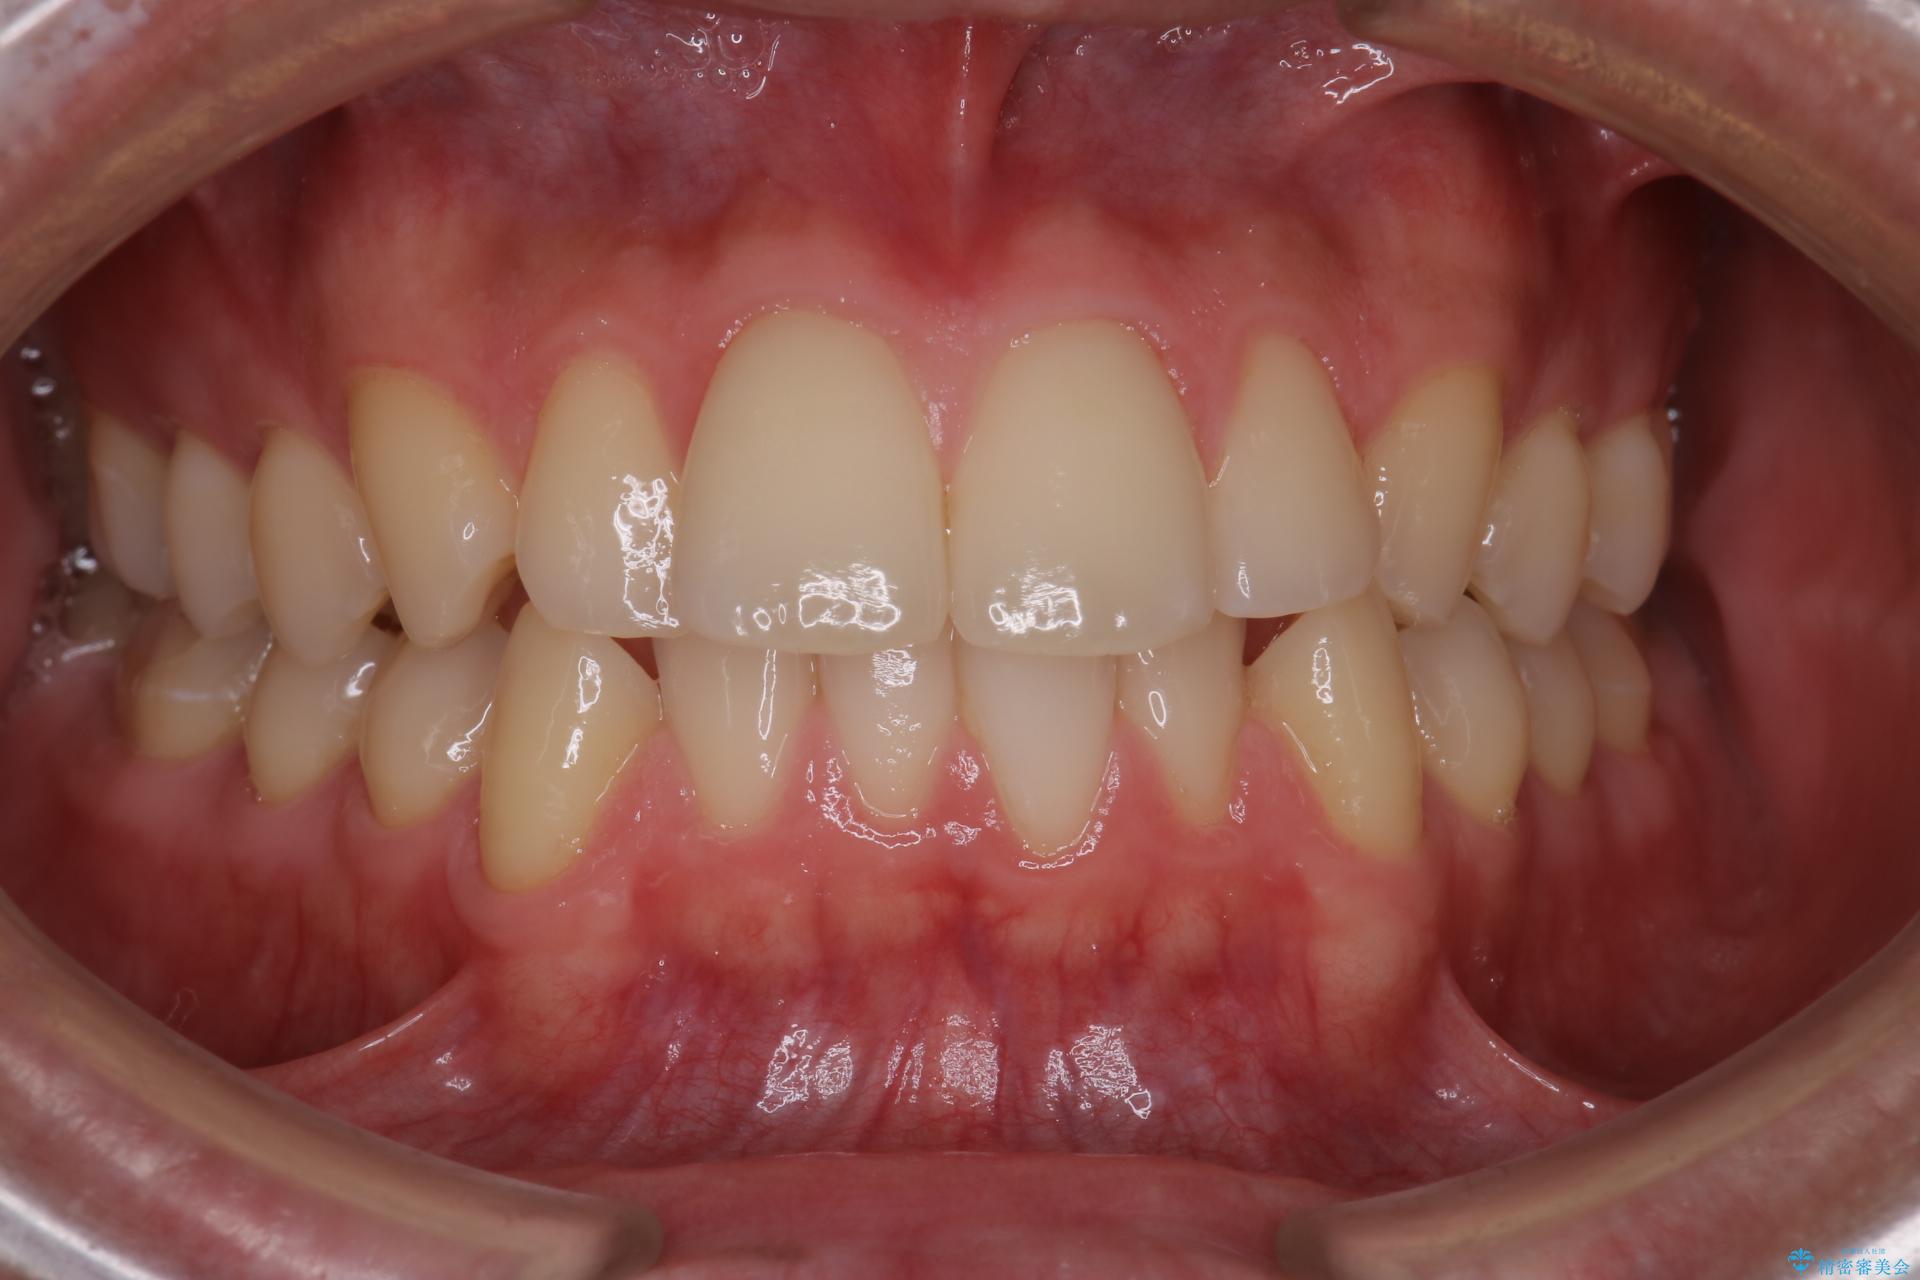

患者様はシミュレーション通りに歯が動くのかと心配されていました。

可能な限り計画通りに歯を動かすために、マウスピース1枚あたりの使用時間を長めに使っていただきました。

そのため、多少治療期間が延びましたが、リファイメント(マウスピースの再発注)なしで終了することができました。